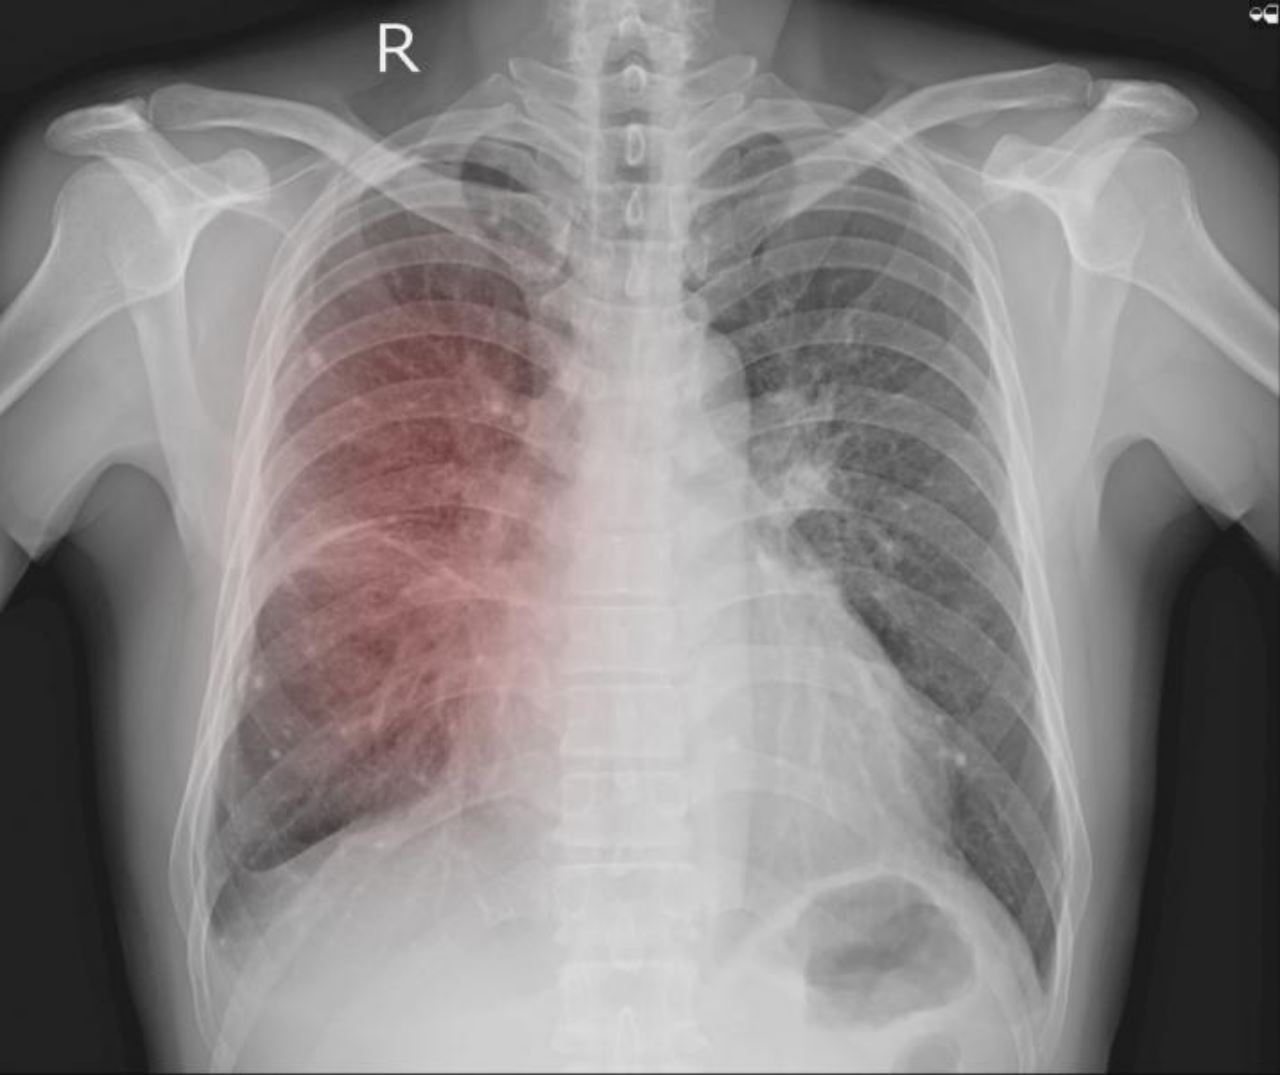

Tiga daripada sembilan individu yang dijangkiti pneumonia atau radang paru-paru misteri dilaporkan meninggal dunia awal bulan ini di Argentina.

Menurut BBC, enam pesakit pertama mula menunjukkan gejala antara 18 dan 23 Ogos. Gejala yang ditunjukkan adalah seperti demam panas, sakit badan dan kesukaran bernafas. Keadaan ini menurut Menteri Kesihatannya adalah sangat serupa dengan COVID-19.